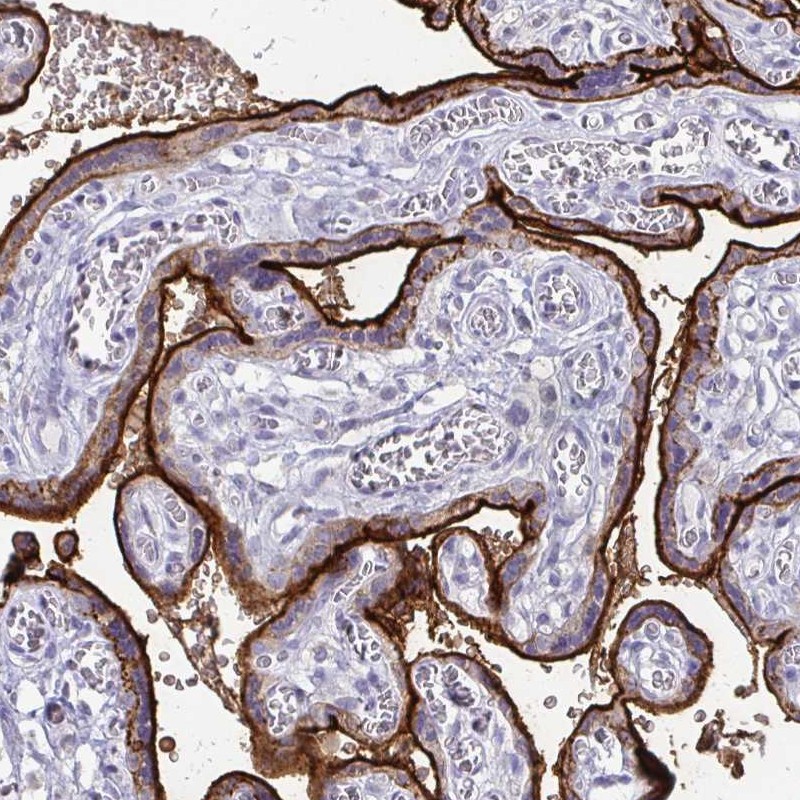

Immunohistochemical staining of human placenta shows strong membranous positivity in trophoblastic cells.